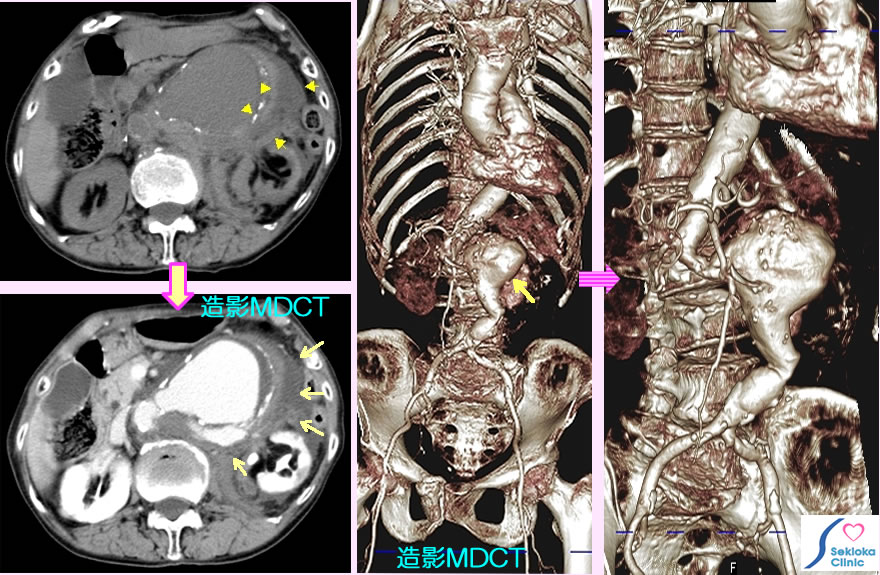

動脈瘤破裂例

動脈瘤破裂部位によって症状は異なります。添付画像の例は 突然の腹痛で来院。

CT、MDCTがより精確(詳細)に判断できる。腹部などでは超音波エコーも有用。添付画像では 上段左のCT(造影剤なし)検査で 黄色矢印で示す部位に動脈瘤からの腹腔内への出血と考えれる所見を認め、造影MDCTで検査を緊急で施行(3次元画像)

少量出血の場合は待機的な場合もありますが、緊急手術。本例も破裂による出血は重篤で救急車で転送。残念ながら約12時間後、他界された。